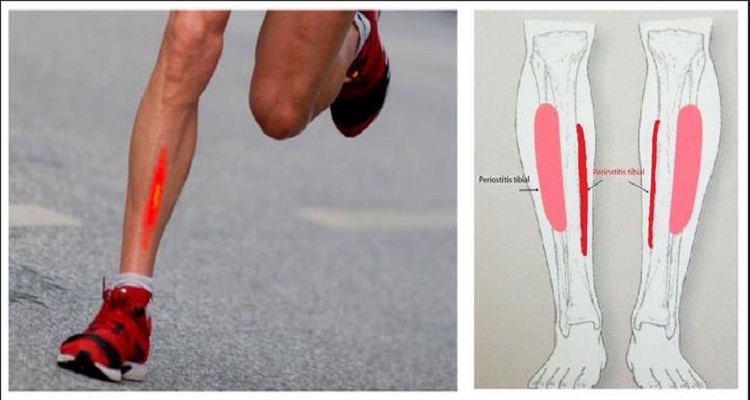

Возможные причины болей в ноге ниже колена и рекомендации